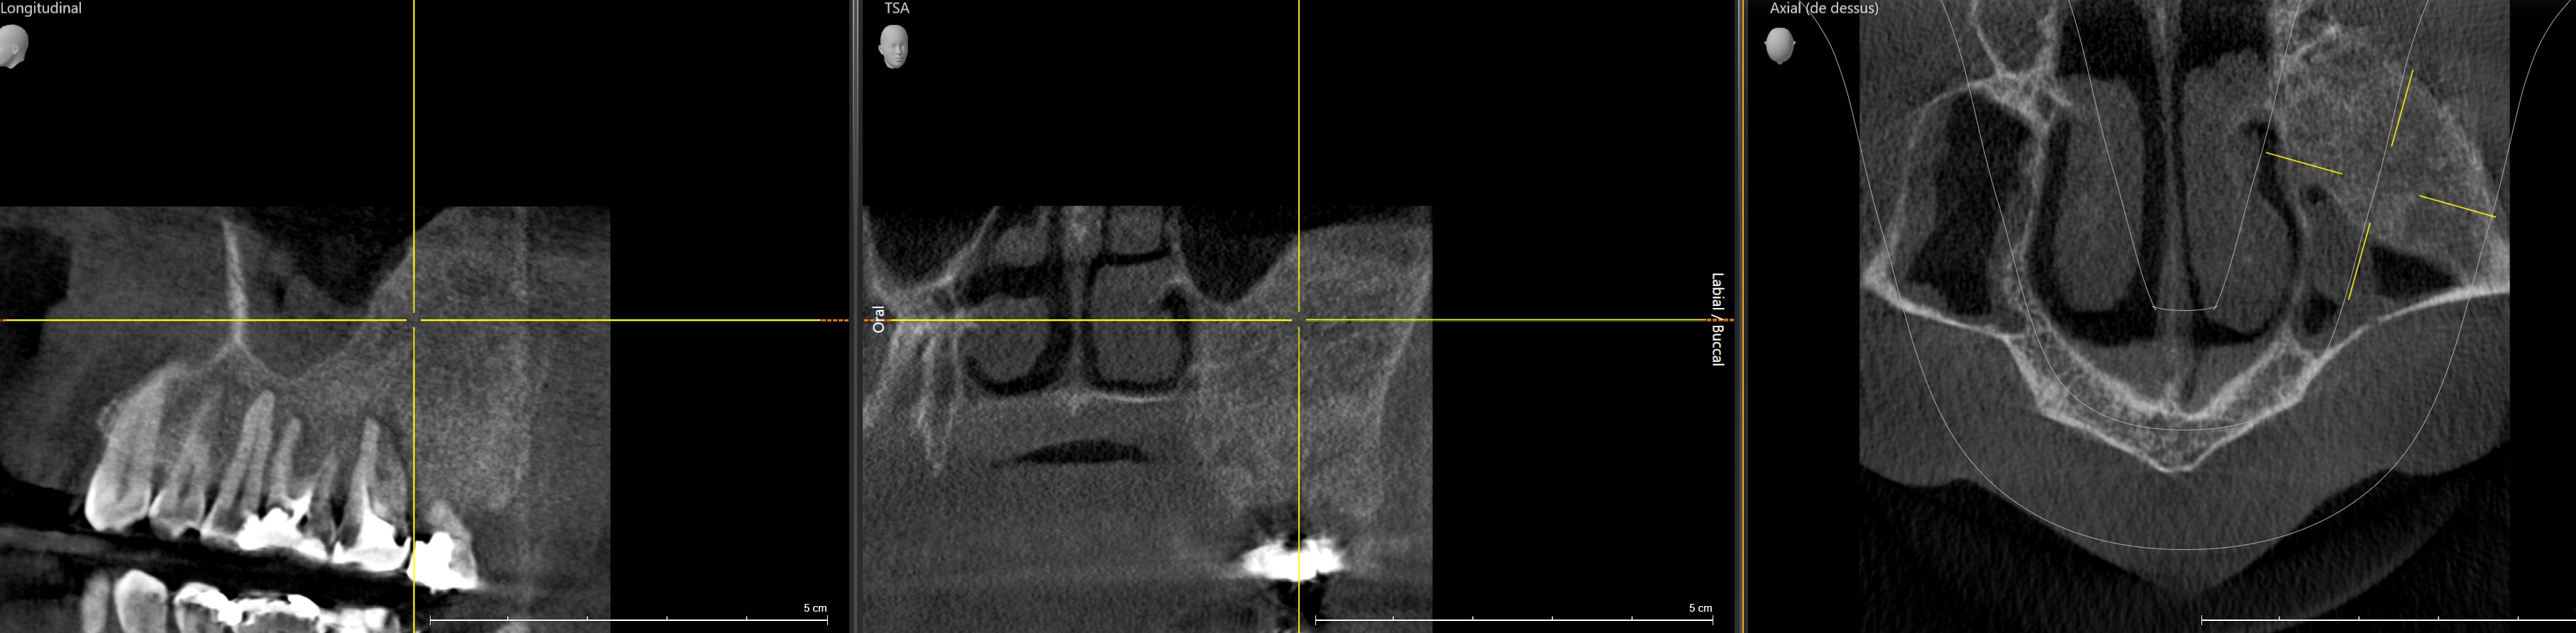

Une dissymétrie au niveau des processus alvéolaires me choque.

Cone beam.

Il y a quand même beaucoup d'os à gauche.

Tu adresses à un stomato / chir oral / maxillo-facial. Ça peut être un osteome…